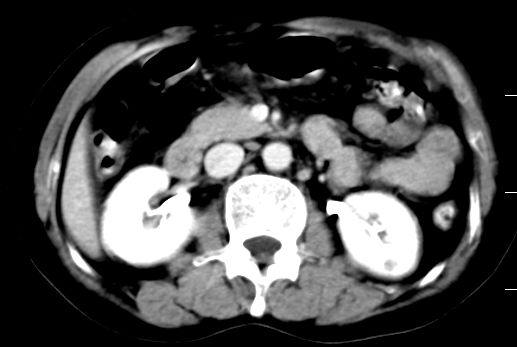

双肾灌注良好,代谢增快,动脉期肾盂见造影剂,左肾下极背侧见一略低密度病灶,延迟期见似不强化囊肿,双侧肾上腺未见异常。

胰腺及脾未见异常。肾门水平腹膜后见小淋巴结。腹腔未见积液征象。